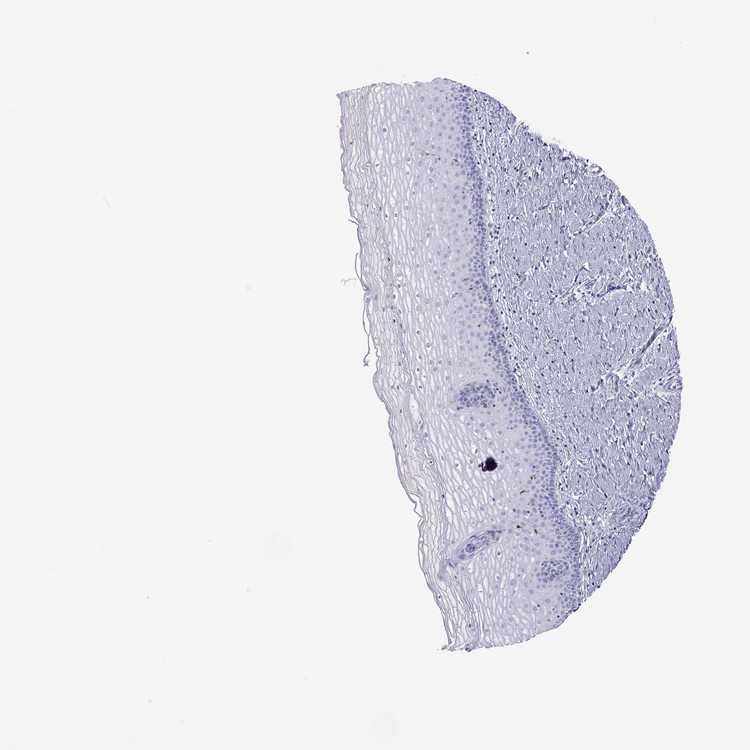

CERVIX - Antibody stainingi

Antibody staining in the annotated cell types in the current human tissue is reported as not detected, low, medium, or high, based on conventional immunohistochemistry profiling in selected tissues. This score is based on the combination of the staining intensity and fraction of stained cells.

Each image is clickable and will lead to virtual microscopy that enables deeper exploration of all samples and also displays staining intensity scores, fraction scores and subcellular localization as well as patient and tissue information for each sample.

Antibody HPA073187

Glandular cells Not detected

Squamous epithelial cells Not detected